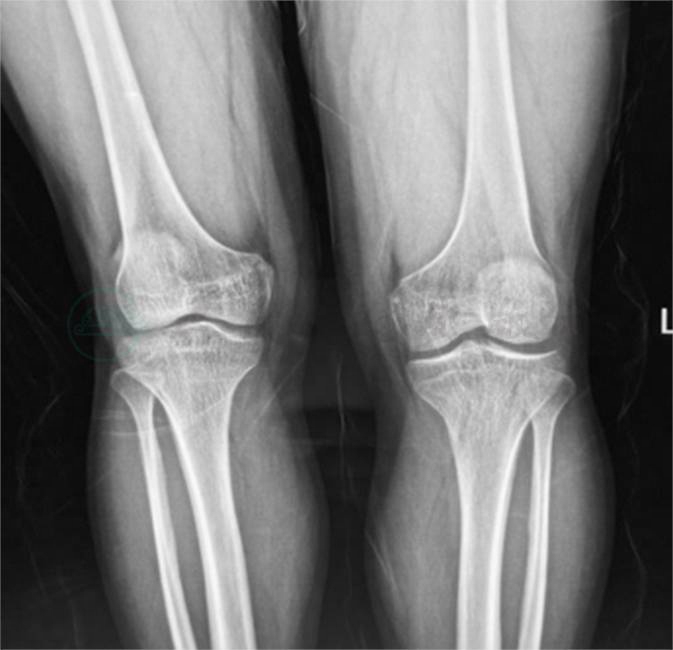

8.双膝关节正位片(图5)双膝关节可见骨质疏松,右膝关节间隙外侧稍变窄。

图5 双膝关节正位片